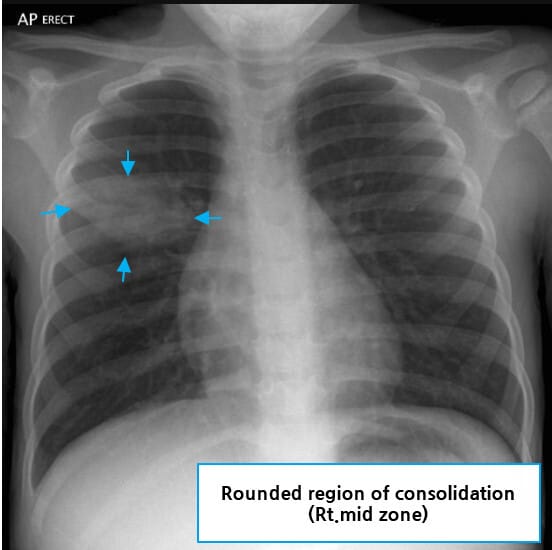

영상 소견

흉부 X선 또는 CT는 폐렴의 진단에서 가장 중요한 영상 도구로, 병변의 형태와 위치를 통해 전형적/비전형적 양상을 구분할 수 있습니다.

전형적 폐렴

| 전형적 폐렴 |

| 🟨 폐엽성 침윤(Lobar consolidation) |

| 한 엽에 국한된 균질한 음영 증가를 말합니다. 폐포 내 삼출물로 인한 폐엽성 폐렴 소견입니다. |

| 🟨 기관지 공기음영(Bronchogram sign) |

| 침윤된 폐포 속에서 공기가 남아 있는 기관지가 선명히 보이며, 폐렴을 시사합니다. |

Gaillard F, Round pneumonia. Case study, Radiopaedia.org (Accessed on 24 Jun 2025) https://doi.org/10.53347/rID-19638